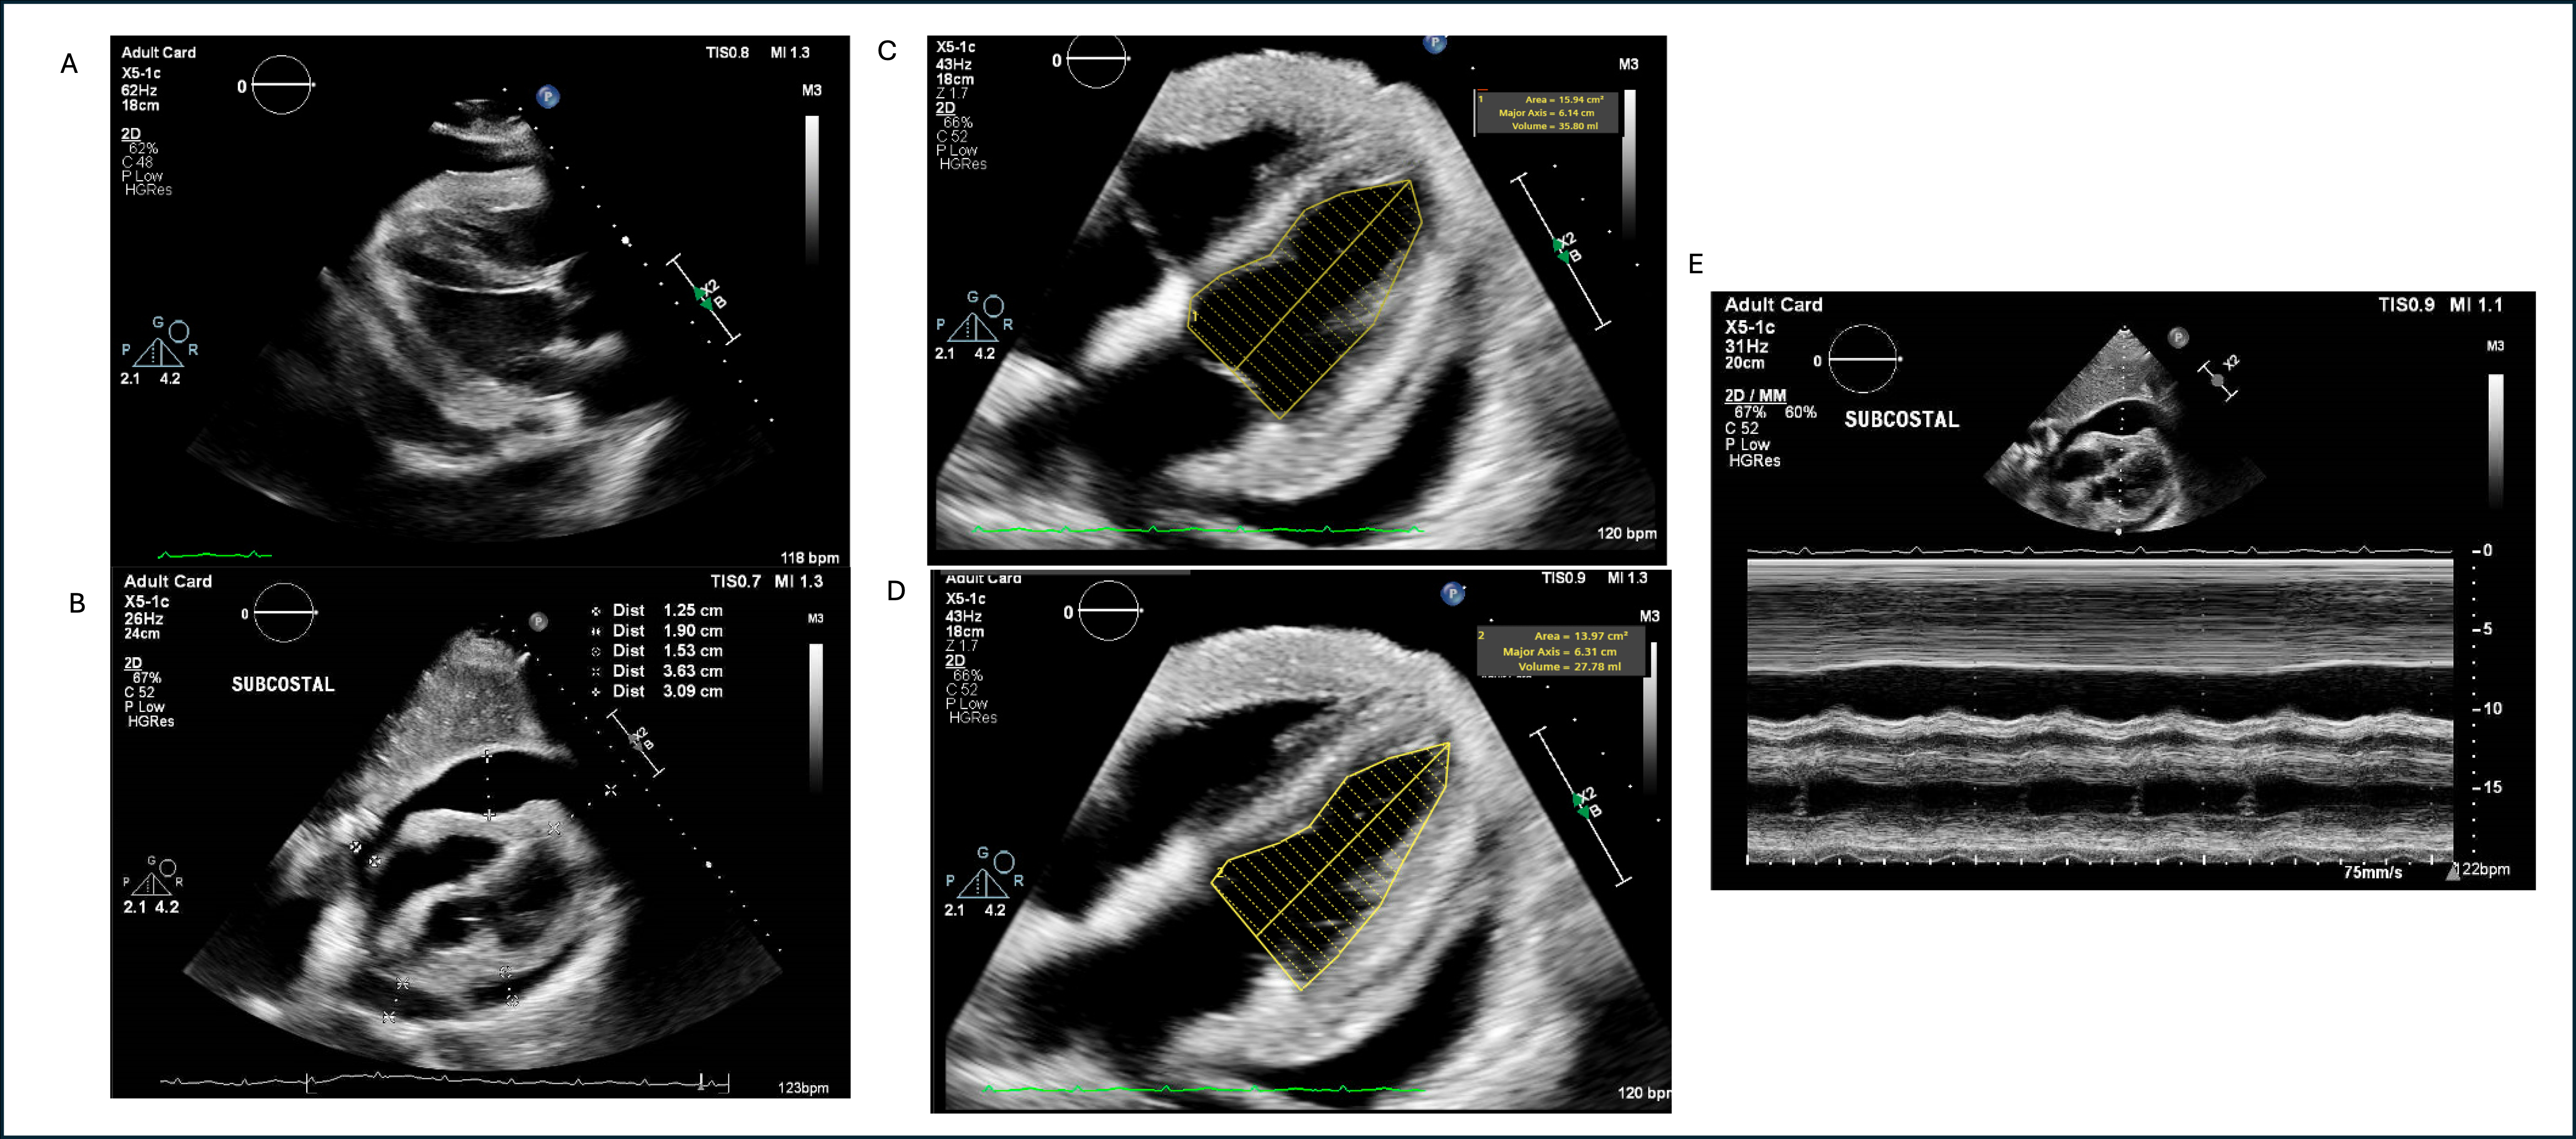

A 63-year-old man with history of Stage 4 Diffuse Large B-Cell Lymphoma and treatment-induced acute myeloid leukemia with incomplete hematologic recovery was admitted for reduced intensity conditioning with fludarabine followed by haplo stem cell transplantation. His prior cancer therapy included rituximab, cyclophosphamide, doxorubicin, vincristine, azacitidine, and venetoclax. He received post-transplant graft-versus-host prophylaxis with cyclophosphamide (PTCy) 50 mg/kg/day on days +3 and +4. On day +8, he became acutely hypotensive with blood pressure 81/61, tachycardic to 152 beats/min, and hypoxic to 86%. Physical exam revealed muffled heart sounds and jugular venous distention. An electrocardiogram showed new atrial flutter and decreased QRS voltage. Labs were notable for BNP 1,118 pg/mL and hs-troponin of 50 ng/L. He was started on norepinephrine and intubated for respiratory distress. Transthoracic echocardiogram (TTE) showed a large pericardial effusion with tamponade, reduction in LVEF from 50-55% to 20-25% and increased biventricular wall thickness. He underwent pericardiocentesis with removal of 700 mL of serous fluid. He was cross titrated to dobutamine for cardiogenic shock, which resolved within days. Cardiac MRI (CMR) on day +26 showed severe diffuse myocardial edema, diffuse midmyocardial late gadolinium enhancement, and pericardial enhancement. In this clinical setting, this was felt to be consistent with fulminant cyclophosphamide myopericarditis (Cy-MP). Subsequent TTE showed recovery of LVEF. He later developed aspiration, bacteremia, and graft failure and expired from septic shock.